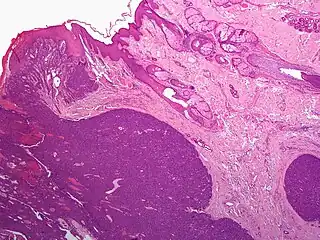

| Micrograph showing an acrospiroma. H&E stain. | |

Hidradenoma refers to a benign adnexal tumor of the apical sweat gland.[1][2] These are 1–3 cm translucent blue cystic nodules. It usually presents as a single, small skin-colored lesion, and may be considered closely related to or a variant of poromas.[3] Hidradenomas are often sub-classified based on subtle histologic differences, for example:[4]